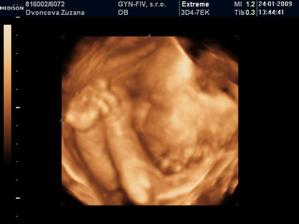

24.1.2009 nám pán doktor prezradil na 3D, že čakáme chlapčeka :o) ....po dlhom rozhodovani sme si povedali, ze to bude maly Nicolas...uz sa velmi tesime, ked pride na svet...caka ho tu cela velka rodina, ktora ho uz teraz velmi lubi :o))